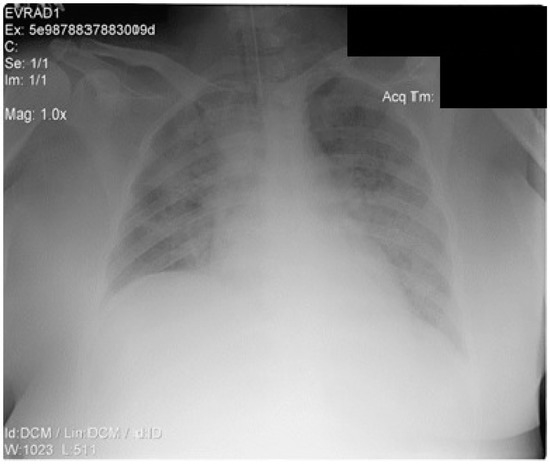

Despite the administration of supplemental oxygen, followed by a high-flow nasal cannula, the respiratory function declined rapidly. The chest X-ray is shown in Figure 2. The patient required intubation and protective mechanical ventilation on day 1, soon after being admitted to the ICU for severe ARDS (P/F < 150), along with increasing oxygen requirements (FiO2 up to 70%), higher PEEP levels, continuous sedation, and neuromuscular blockade. Repeated PCR SARS-COV-2 tests were performed upon admission, day 4, day 9, day 14, and day 36, all with negative results.

Figure 2. Thorax X-ray after intubation (anteroposterior view).